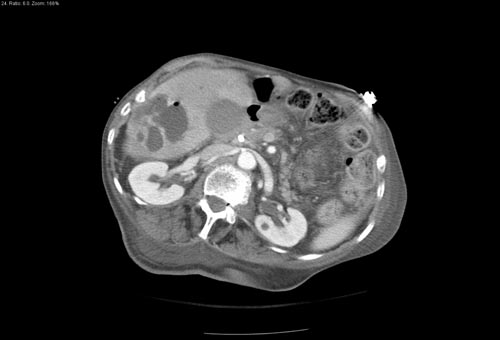

El ultrasonido mamario utiliza ondas sonoras para generar imágenes del tejido mamario en tiempo real, sin emplear radiación. Este estudio es especialmente útil para diferenciar entre masas sólidas y quísticas, identificar lesiones que no son visibles en la mastografía y evaluar áreas específicas que el médico considera sospechosas.

Cuando la mastografía muestra hallazgos dudosos, el ultrasonido puede proporcionar información adicional que ayuda a caracterizar mejor las lesiones y decidir si es necesario realizar una biopsia u otro procedimiento.